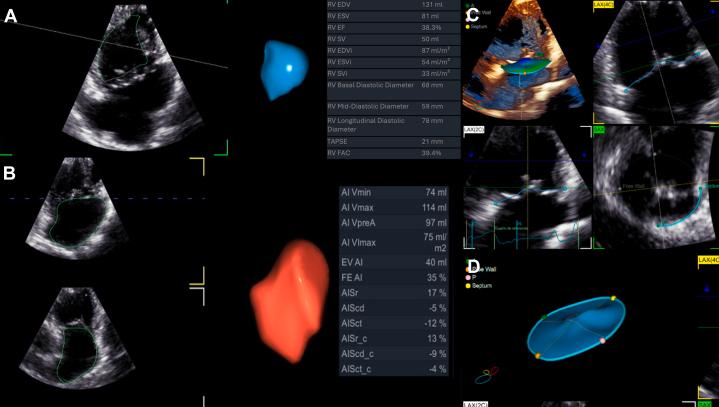

Double-Outlet Right Ventricle in an Adult With a Univentricular Heart and Total Situs Inversus.

Double-outlet right ventricle is a complex conotruncal anomaly in which both great arteries arise predominantly from the right ventricle. The coexistence of total situs inversus and univentricular physiology is exceedingly rare.

CASE SUMMARY

A 38-year-old man presented with severe chronic cyanosis (baseline oxygen saturation 65%), NYHA functional class III dyspnea, and right-sided heart failure. Multimodal imaging (echocardiography, CT, and cardiac magnetic resonance) confirmed total situs inversus, a markedly hypoplastic left ventricle anatomically isolated by a muscular ridge, and double-outlet right ventricle with moderate subpulmonary stenosis. His condition was stabilized medically, but surgical risk was deemed prohibitive owing to his univentricular physiology.

DISCUSSION

This case underscores the critical importance of comprehensive imaging for delineating complex intracardiac anatomy and illustrates how moderate subpulmonary stenosis can temper pulmonary overcirculation, thereby prolonging survival.

TAKE-HOME MESSAGE: Meticulous anatomical definition is essential for managing rare adult congenital heart disease.